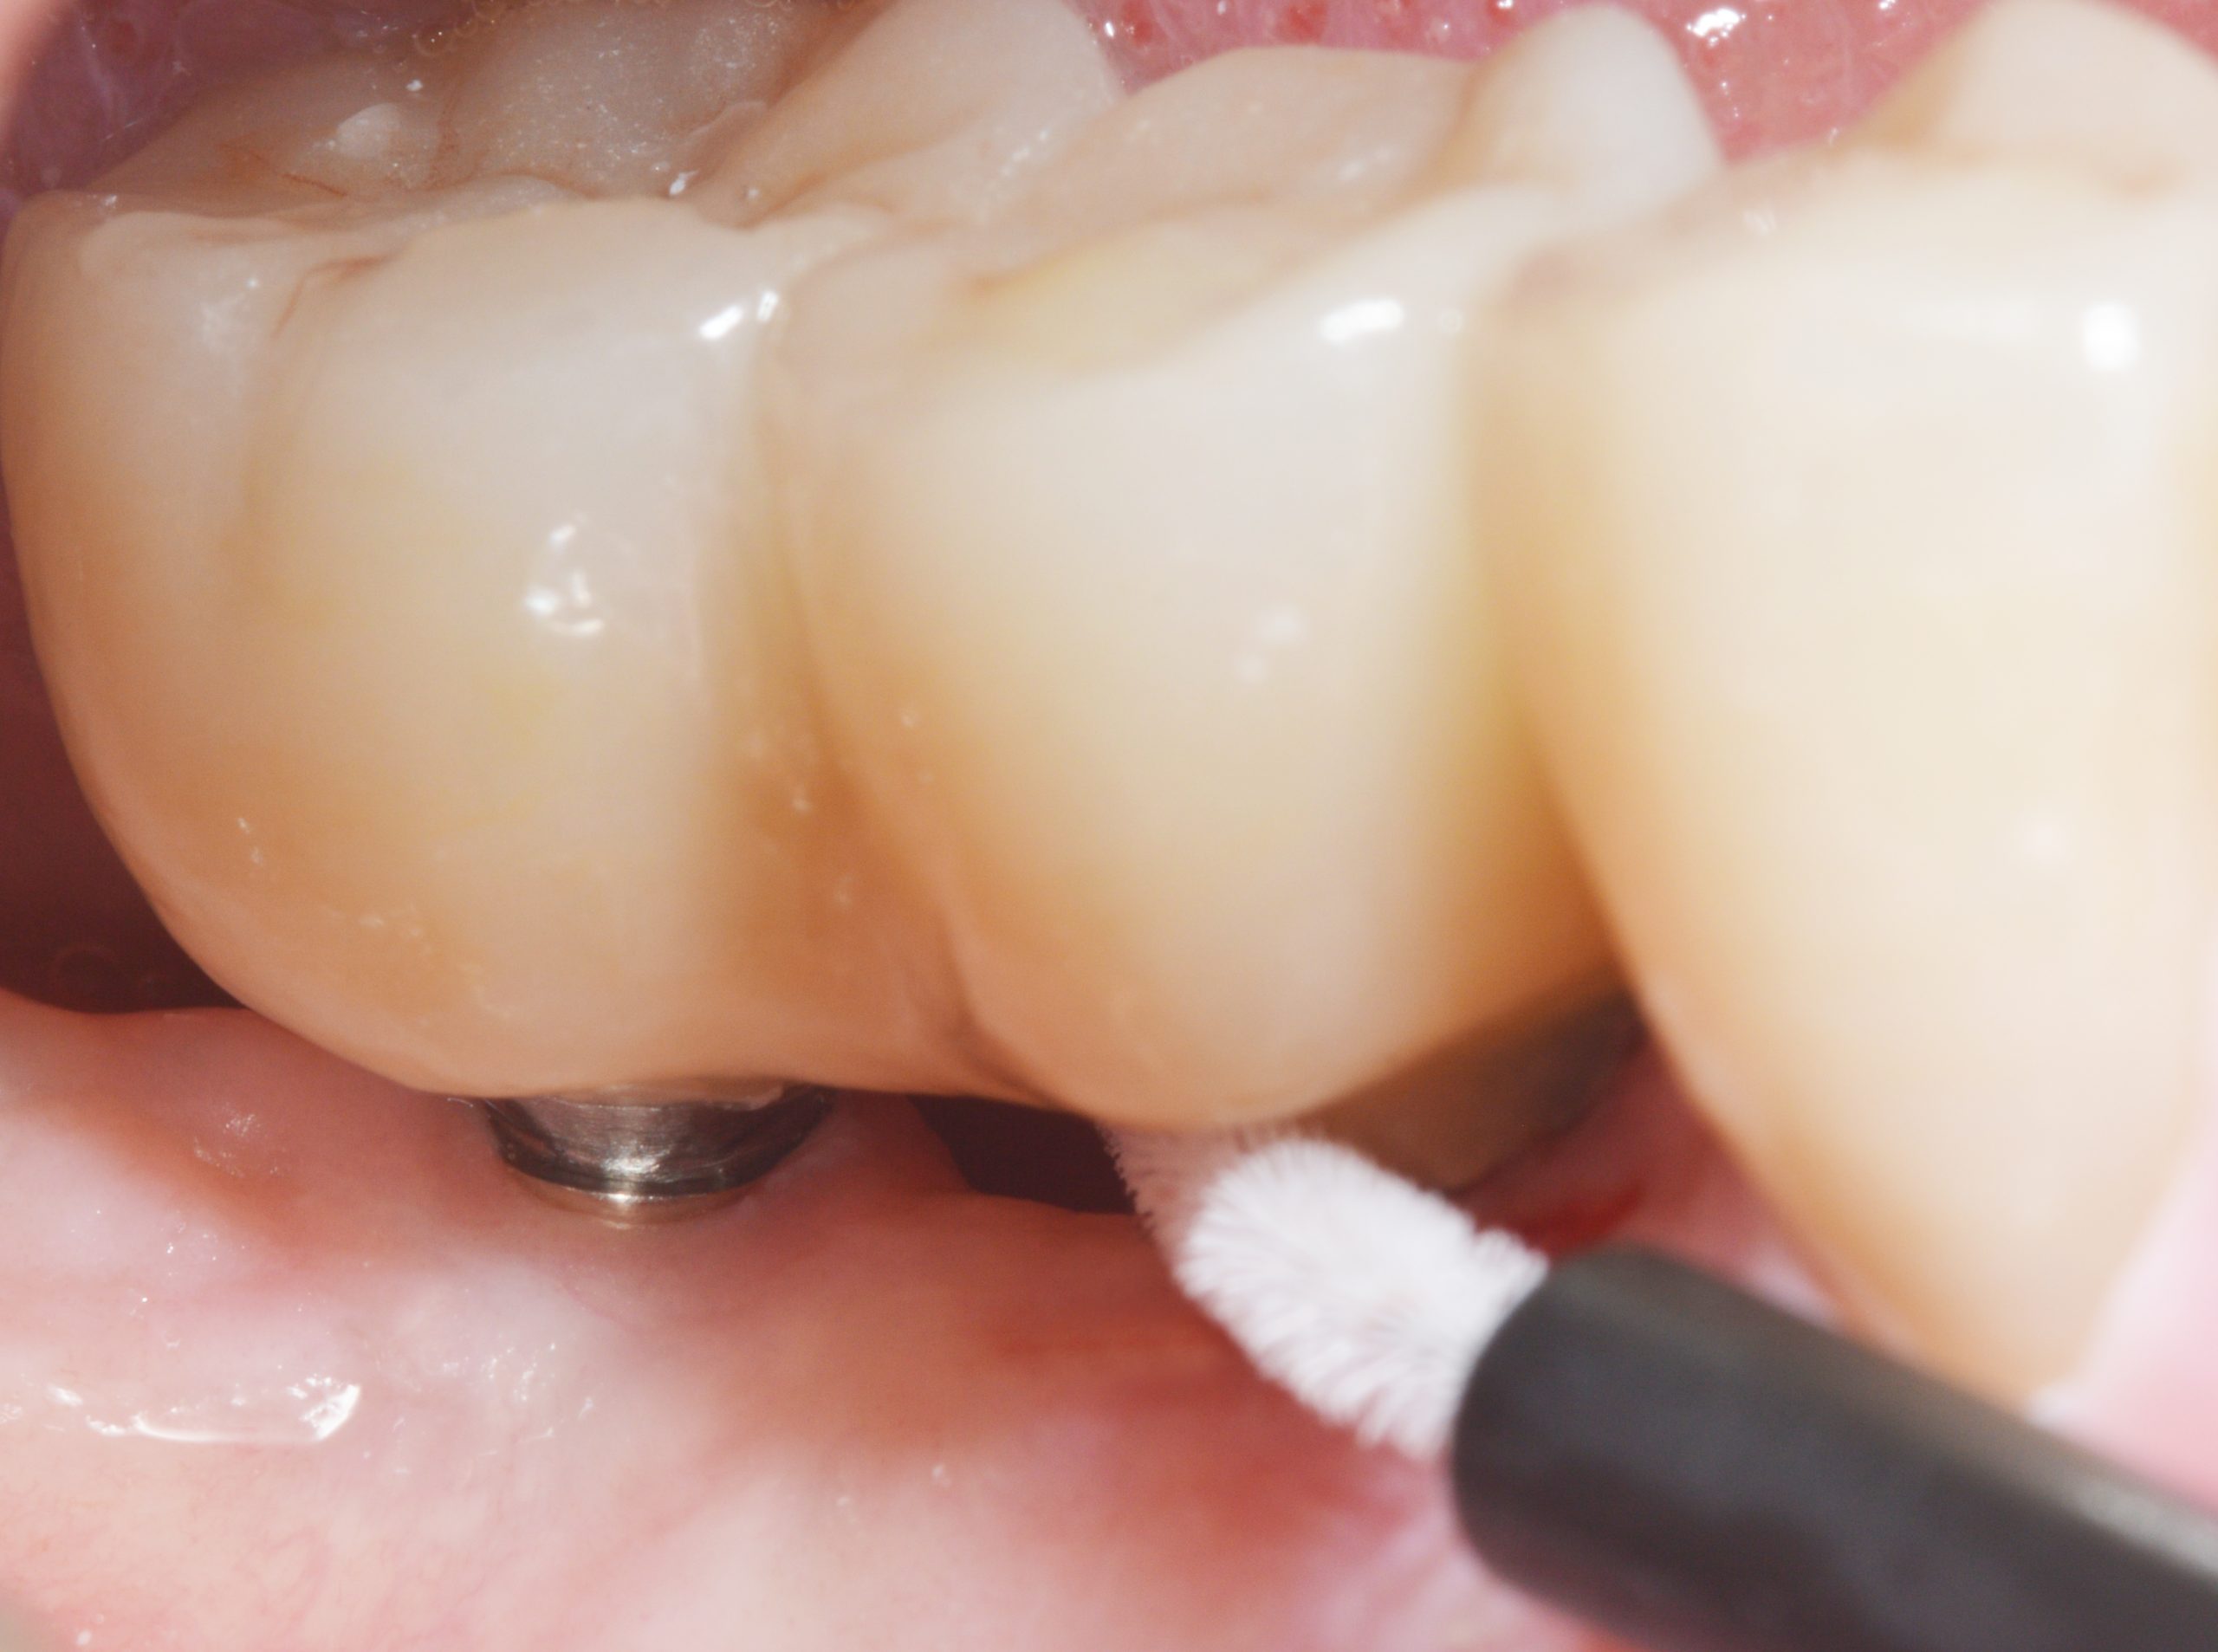

During open healing, cleaning checks were carried out with instructions to also clean the cover screws using special brushes to ensure an inflammation-free peri-implant gingiva.

Due to the open healing, surgical exposure was not necessary. The Ostell was used to document the strength, which was well above 70 ISQ for both implants. Gingival conditions before the impression was taken were clean.

In addition, the dental technicians ensured a cleaning-friendly basal passage between 45 and 46. The handling of the interdental brushes was checked and the patient was instructed to attend a regular recall.